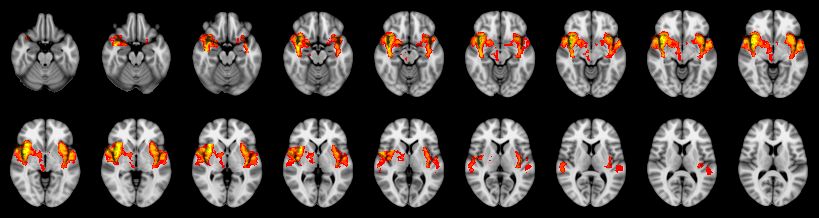

Combined

Tippett:

Fisher: